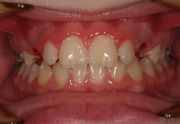

.... griglia linguale ( solo 4 mesi) e successivamente con Barra palatale in intrusione (discostata dal palato),in contemporanea al dispositivo elastodontico. Sono state associate sedute di terapia miofunzionale logopedica. Il caso e' ancora sotto controllo ma la durata di trattamento effettiva e' stata di anni 2!.